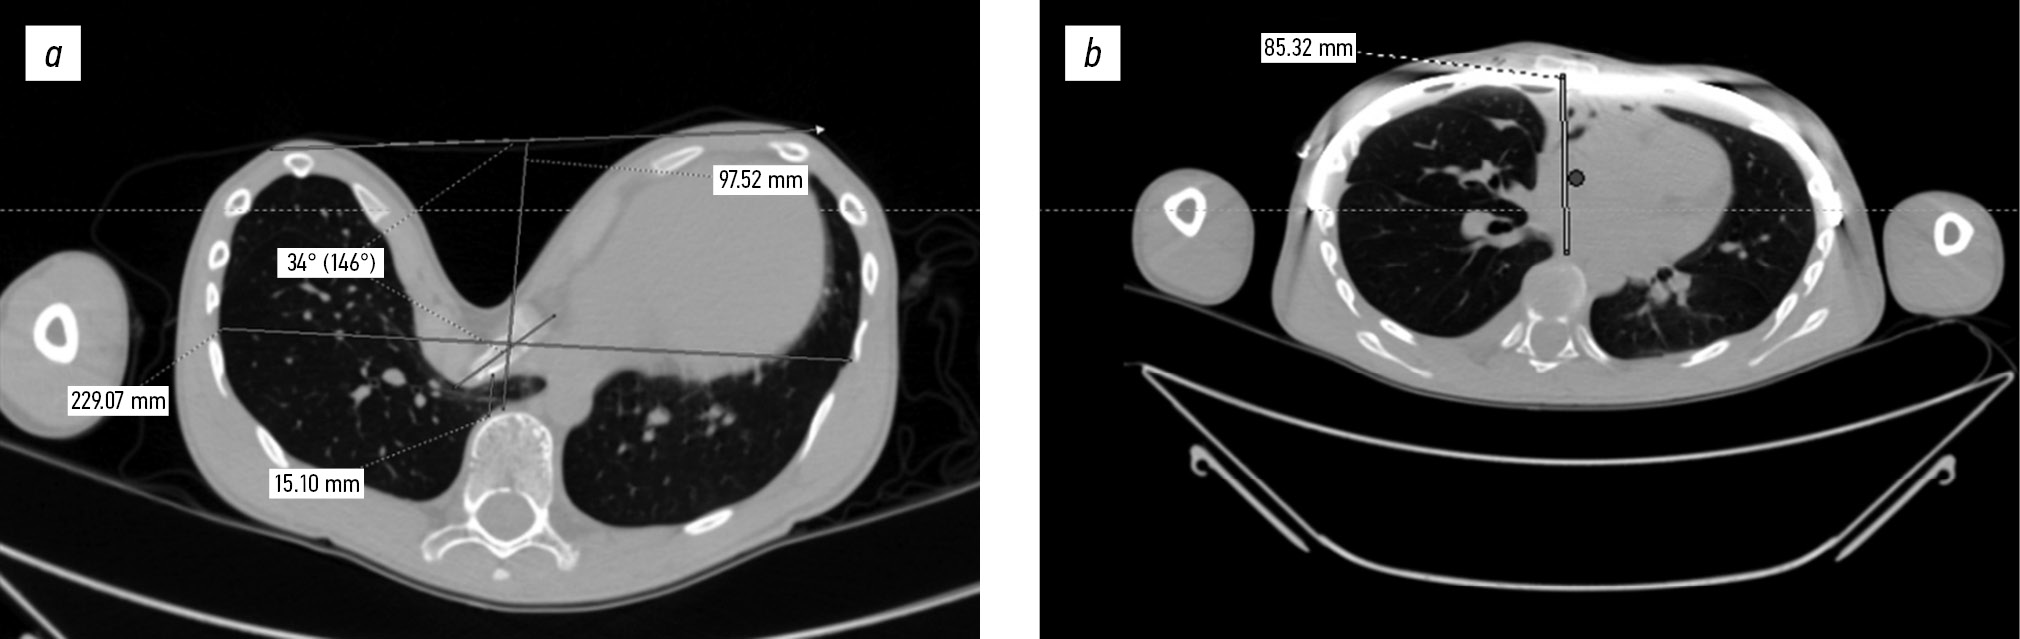

Компьютерная томография грудной клетки: определена деформация грудной клетки с воронкообразным компонентом, асимметричным, индекс Галлера 15,170 / индекс компрессии 0,154 / угол грудино-реберного комплекса 34° правосторонний. Консолидированная стернотомия в условиях проволочных серкляжных швов на 6 уровнях, дистальный край грудины в непосредственной близости от вентральной поверхности позвоночника и магистральных сосудов (аорта, нижняя полая вена). Определено опорное полукольцо сердца (пластика митрального клапана).

Рис. 5. Компьютерные томограммы до и после коррекции: a — исходный размер ретростернального пространства, до операции; б — контрольное исследование на 5-е сутки после операции.

Рис. 6. Компьютерные томограммы до и после коррекции: a — до операции; б — 5-е сутки после операции.